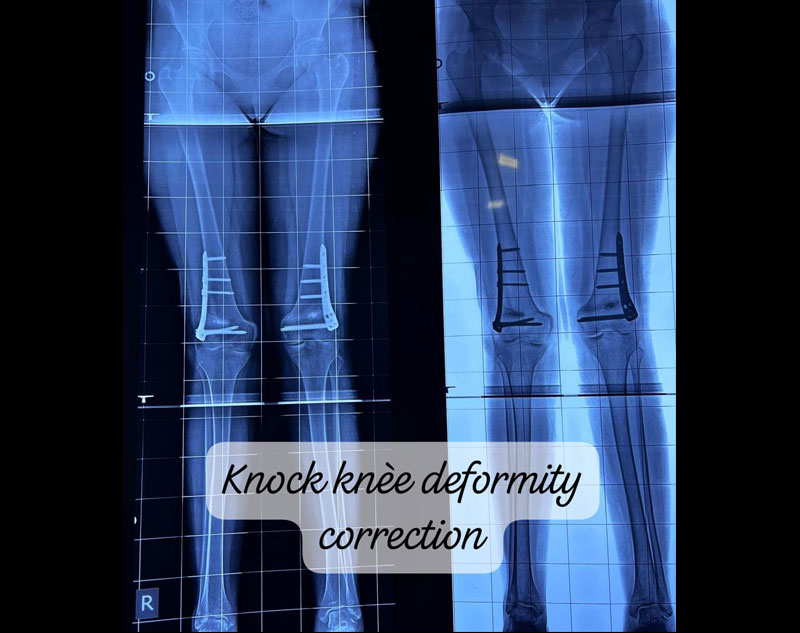

Deformity correction for conditions like knock knees (genu valgum) and bow knees (genu varum) involves surgical and non-surgical treatments aimed at realigning the legs to a more normal, functional position. These conditions can affect walking, cause pain, and lead to long-term joint problems if left untreated.

Knock knees are a condition where the knees angle inward, causing them to touch while the ankles remain apart. This misalignment can cause abnormal walking patterns, joint pain, and even arthritis over time.